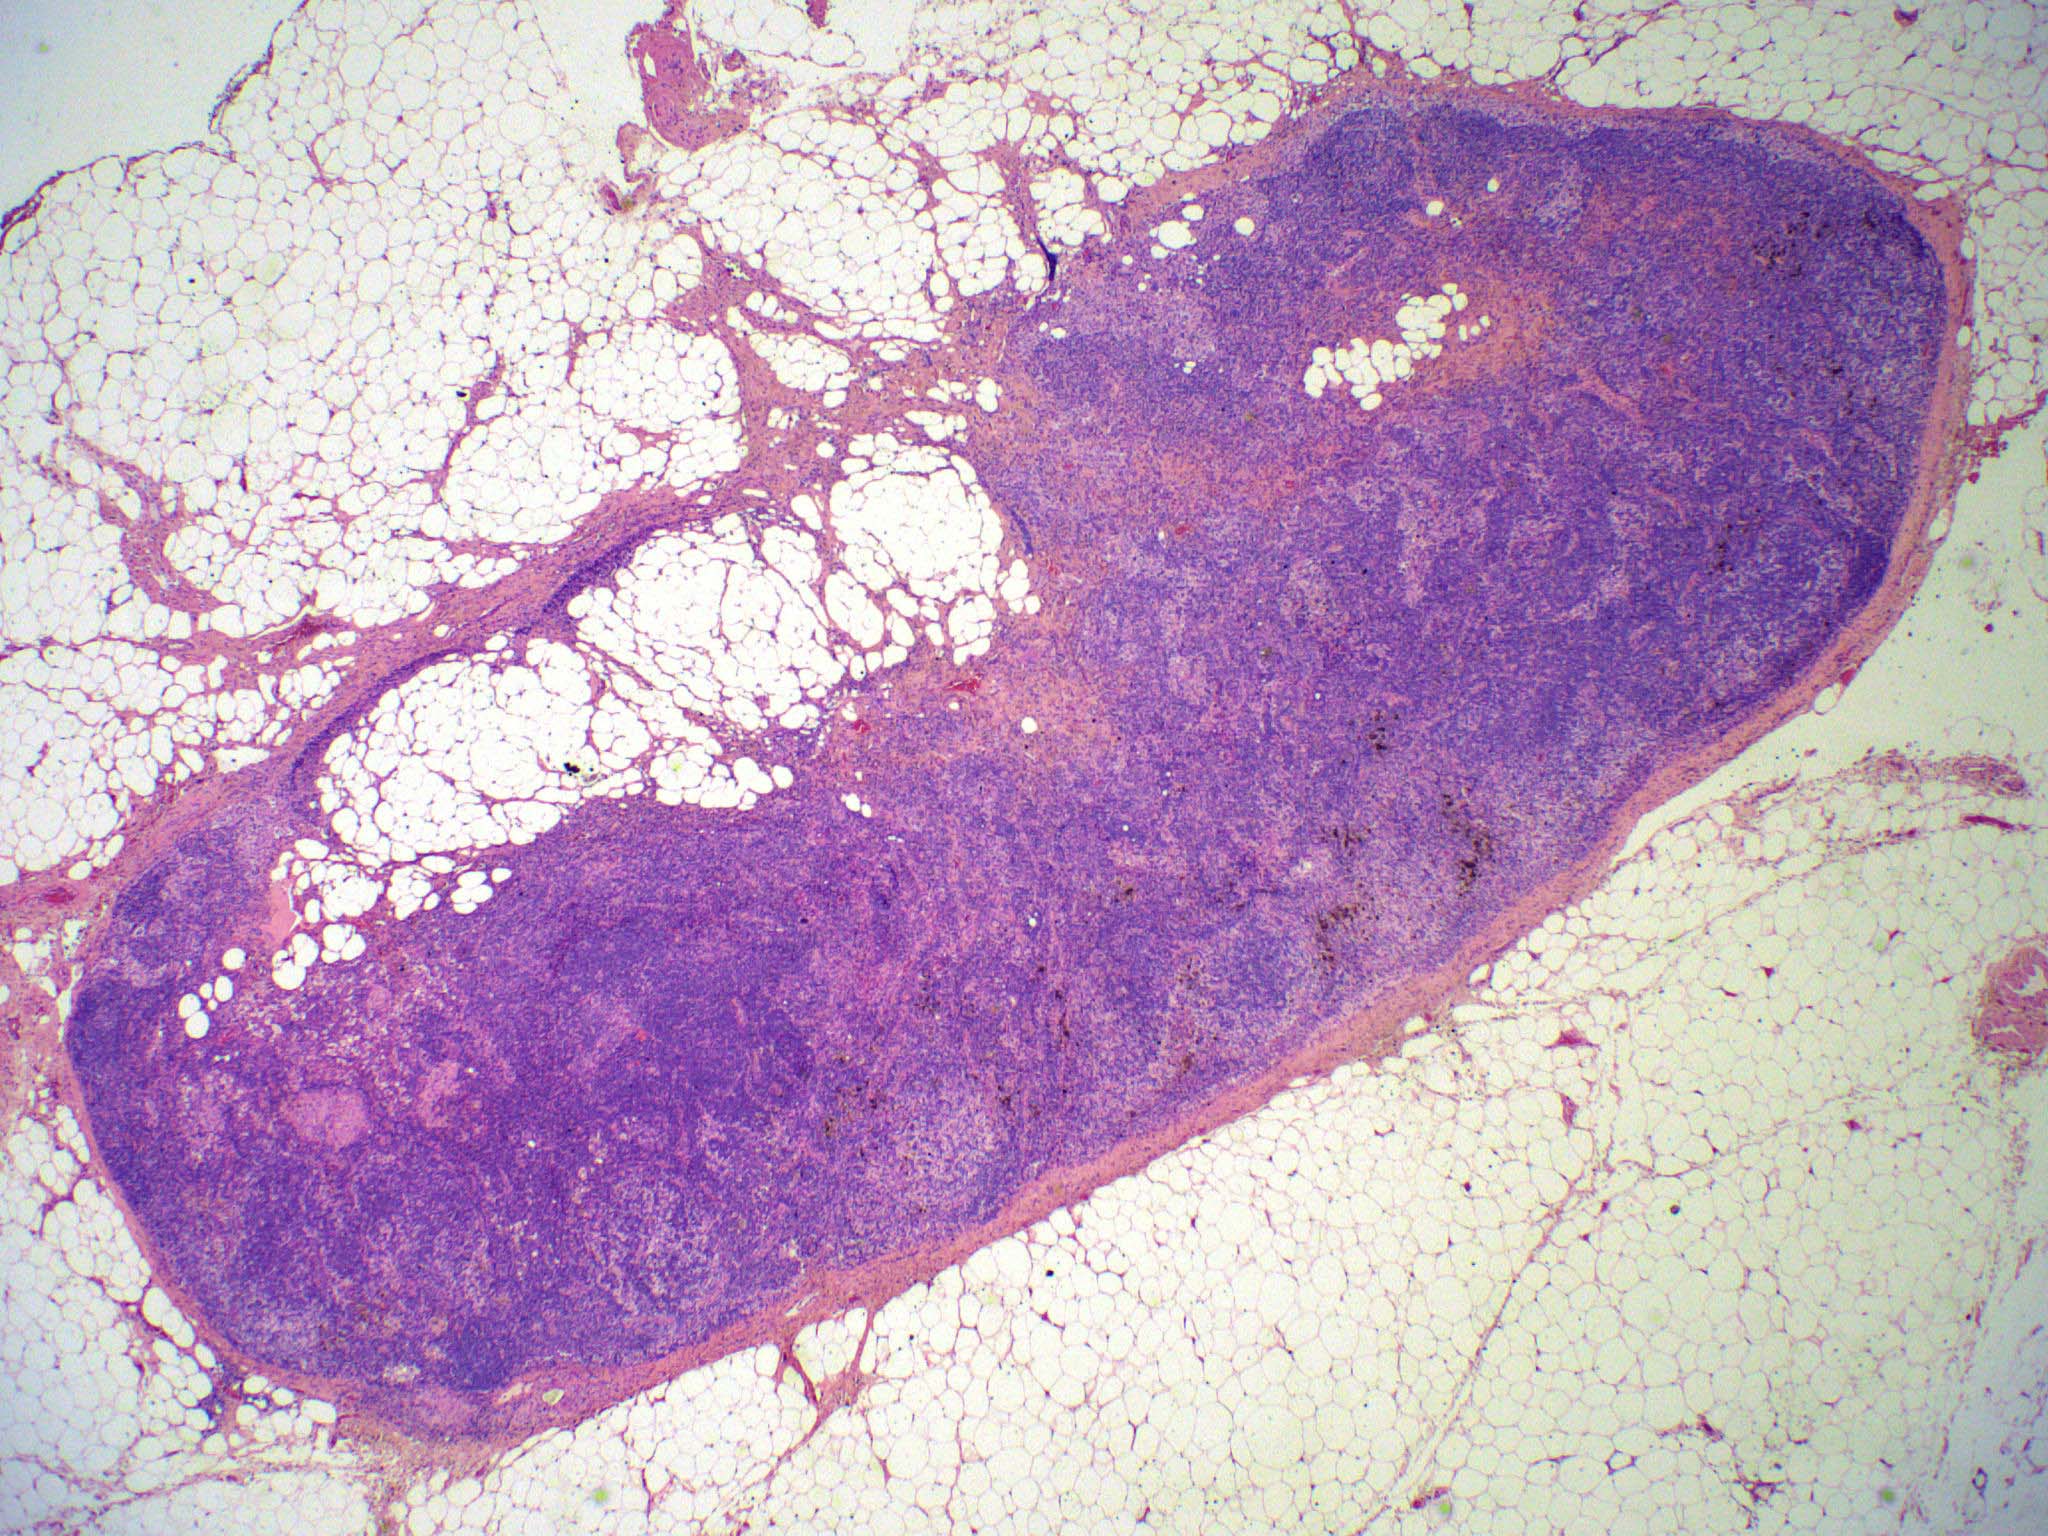

Microscopic (histologic) images

Contributed by Ingrid Tam, M.D., M.Sc., Emina Emilia Torlakovic, M.D., Ph.D. and Nikhil Sangle, M.D. (Case #396)

Microscopic (histologic) description

- There is always preserved nodal architecture with intact capsule

- Follicular hyperplasia may be present but it is usually minimal

- Spectrum of changes from mild to severe, characterized by paracortical expansion with pale, irregularly shaped areas containing numerous pale staining histiocytes, interdigitating dendritic cells, Langerhans cells and occasional immunoblasts